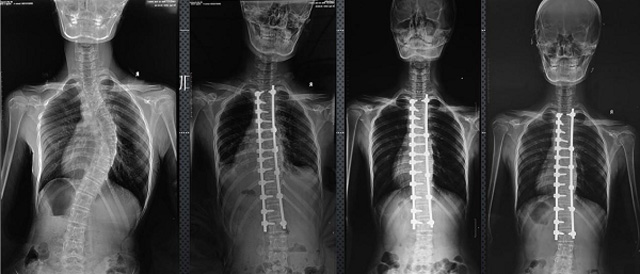

(7)全身拼接功能對有較大尺寸全脊柱拼接圖接桂成金下股分成幾次拍攝,再經過秋件開在骨科開展的全脊柱畸形矯治工作中,雖然CT. MRI也能獲取全脊柱影像,接圖像,以便于長度、角度、力線等測量和察脊柱在重力情況下但不能進行立位檢查,無法觀全景觀察。全身拼接功能是高等級DR攝取患者立位全下的功能狀態圖像,因此采用動態醫院特別看重的動態DR功能之一。注:圖中Cobb脊柱正側位圖像是首選的檢查方法角度的大小是反映側彎嚴重程度的一個標準。